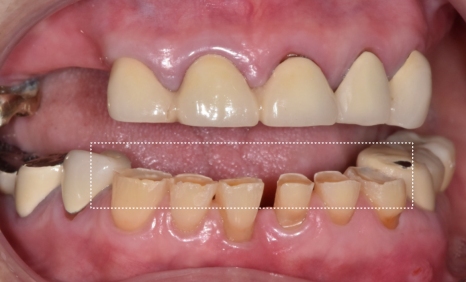

결과적으로,

아래 앞니 7개는 크라운으로 살리고,

총 12대의 임플란트를 더 식립하여

임플란트 보철로 수직 고경을 다시 세우는 방식으로

전체 교합을 재구성했습니다.

치료가 마무리된 뒤

환자분은 거울을 보시더니

“전에는 입이 쏙 들어가 보였는데

이제는 괜찮아 보여요”

라며 환하게 웃으셨습니다.

230211 (전) 240510 (후)